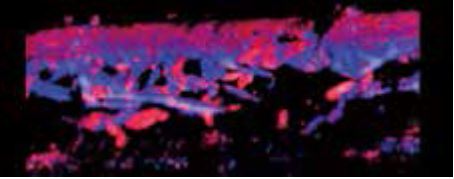

Мікоз фунгоїдний (шкірна Т-клітинна лімфома)

У випадку грибкового мікозу, де товщина ураження становить лише 0,4 мм, надвисокочастотний датчик може чітко візуалізувати злегка потовщений шар ( мал. 4а). Враховуючи розмір, його зазвичай складно спостерігати у відтінках сірого. Після застосування супермікросудинної візуалізації (SMI) ураження чітко відмежоване від нормальної ділянки шкіри, оскільки воно, безумовно, є гіперваскулярним ( мал. 4б). На мал. 4в показано 3D-зображення двох вогнищ ураження. Аваскулярна ділянка між ураженнями представляє нормальну шкіру.

а) Сірошкальне зображення

б) cSMI

в) cSMI з використанням Smart sensor 3D

Малюнок 4. Фунгоїдний мікоз (шкірна Т-клітинна лімфома)